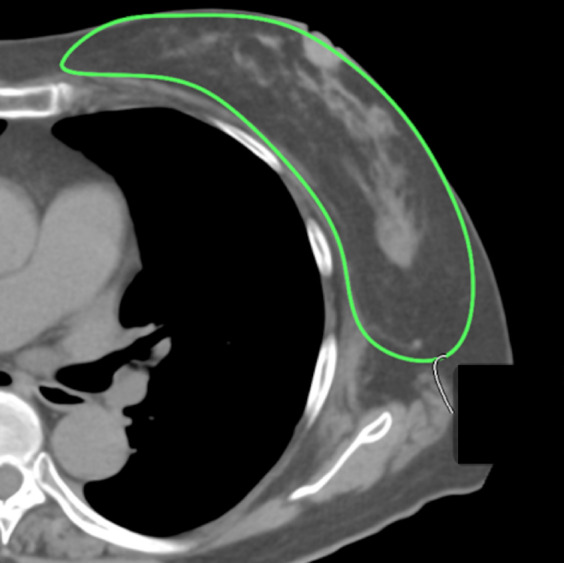

Objective: The utility of three-dimensional surface imaging (3DSI) for measuring breast volume in the upright position has not been established.

Materials and methods: First, the accuracy of 3DSI measurements was evaluated using plastic models with known breast volumes. Then, the breast volumes of 30 patients were measured using 3DSI in the upright position, computed tomography (CT) in the supine position, magnetic resonance imaging (MRI) in the prone position, and mammography (MMG) of the compressed breast. To determine the impact of 3DSI measurements, the correlation coefficients between 3DSI and CT, between MMG and CT, and between MRI and CT were calculated.

Results: The accuracy of 3DSI measurements was confirmed using plastic models. The correlation coefficients between 3DSI and CT, between MRI and CT, and between MMG and CT were 0.83, 0.997, and 0.84, respectively. Although the breast volume measured by 3DSI was closely associated with that measured by CT, this correlation was weaker than that between the MRI- and CT-measured volumes and comparable with that between the MMG- and CT-measured volumes.

Conclusion: 3DSI can be used to measure breast volume in the upright position with clinically acceptable accuracy for the evaluation of cosmetic surgical outcomes.